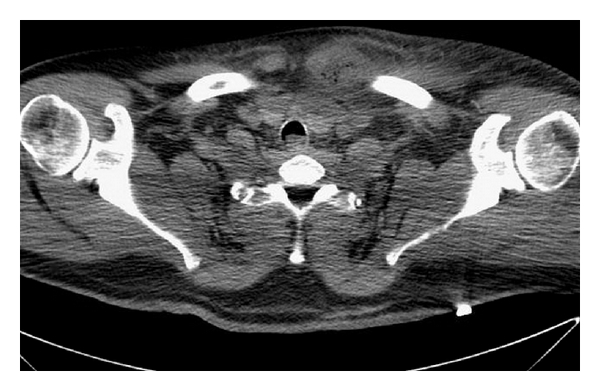

Our study was approved by the institutional review board at Houston Methodist Hospital Research Institute. We searched the administrative database at Houston Methodist Hospital for admissions from January 1, 2002, to June 1, 2012, with the diagnosis of osteomyelitis of the shoulder region (ICD-9 Code 730.21) or osteomyelitis of unspecified location (ICD-9 Code 730.20) as there is no ICD-9 code for osteomyelitis of the sternoclavicular joint. Our inclusion criteria were the diagnosis of osteomyelitis of the sternoclavicular joint based on radiographic findings (Figure 1(a)) or findings of sternoclavicular osteomyelitis at the time of initial debridement. We excluded patients who did not have diagnostic tests or treatments performed at our institution. We collected information from patient charts about the date of diagnosis, etiology of infection, organism responsible for infection, and treatment course.

2.1. Preoperative Imaging

Imaging of the chest and lower neck with either CT or MRI was obtained based on clinical suspicion of SCJ infection [1, 2, 10]. Obtaining the study with intravenous contrast use can aid in enhancing the abscess and confirming patency of the arteries that will provide blood flow to the anticipated muscle flap. On imaging, the abscess cavity may or may not contain gas bubbles, and often very high-density fluid within the abscess cavity may track into the neck region or mediastinum.